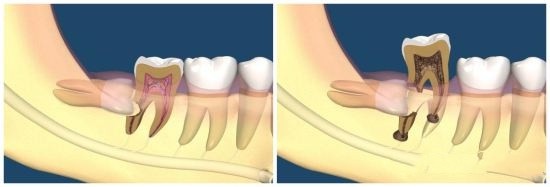

为了长出来,智齿只能“自私”地顶坏前面的牙齿。

这也就是 智齿会引起牙疼、牙龈发炎等问题的原因 。

但凡 位置不正 ,别管属于专业术语中的哪一种类型,都存在萌出顶坏牙齿的风险, 建议拔除 。

尤其是那些“蠢蠢欲动”的智齿,已经引起了牙疼、牙龈发炎等情况,哪怕吃点消炎药将炎症又下去了, 后面也会反复发作,并且一次比一次疼,一次比一次严重。